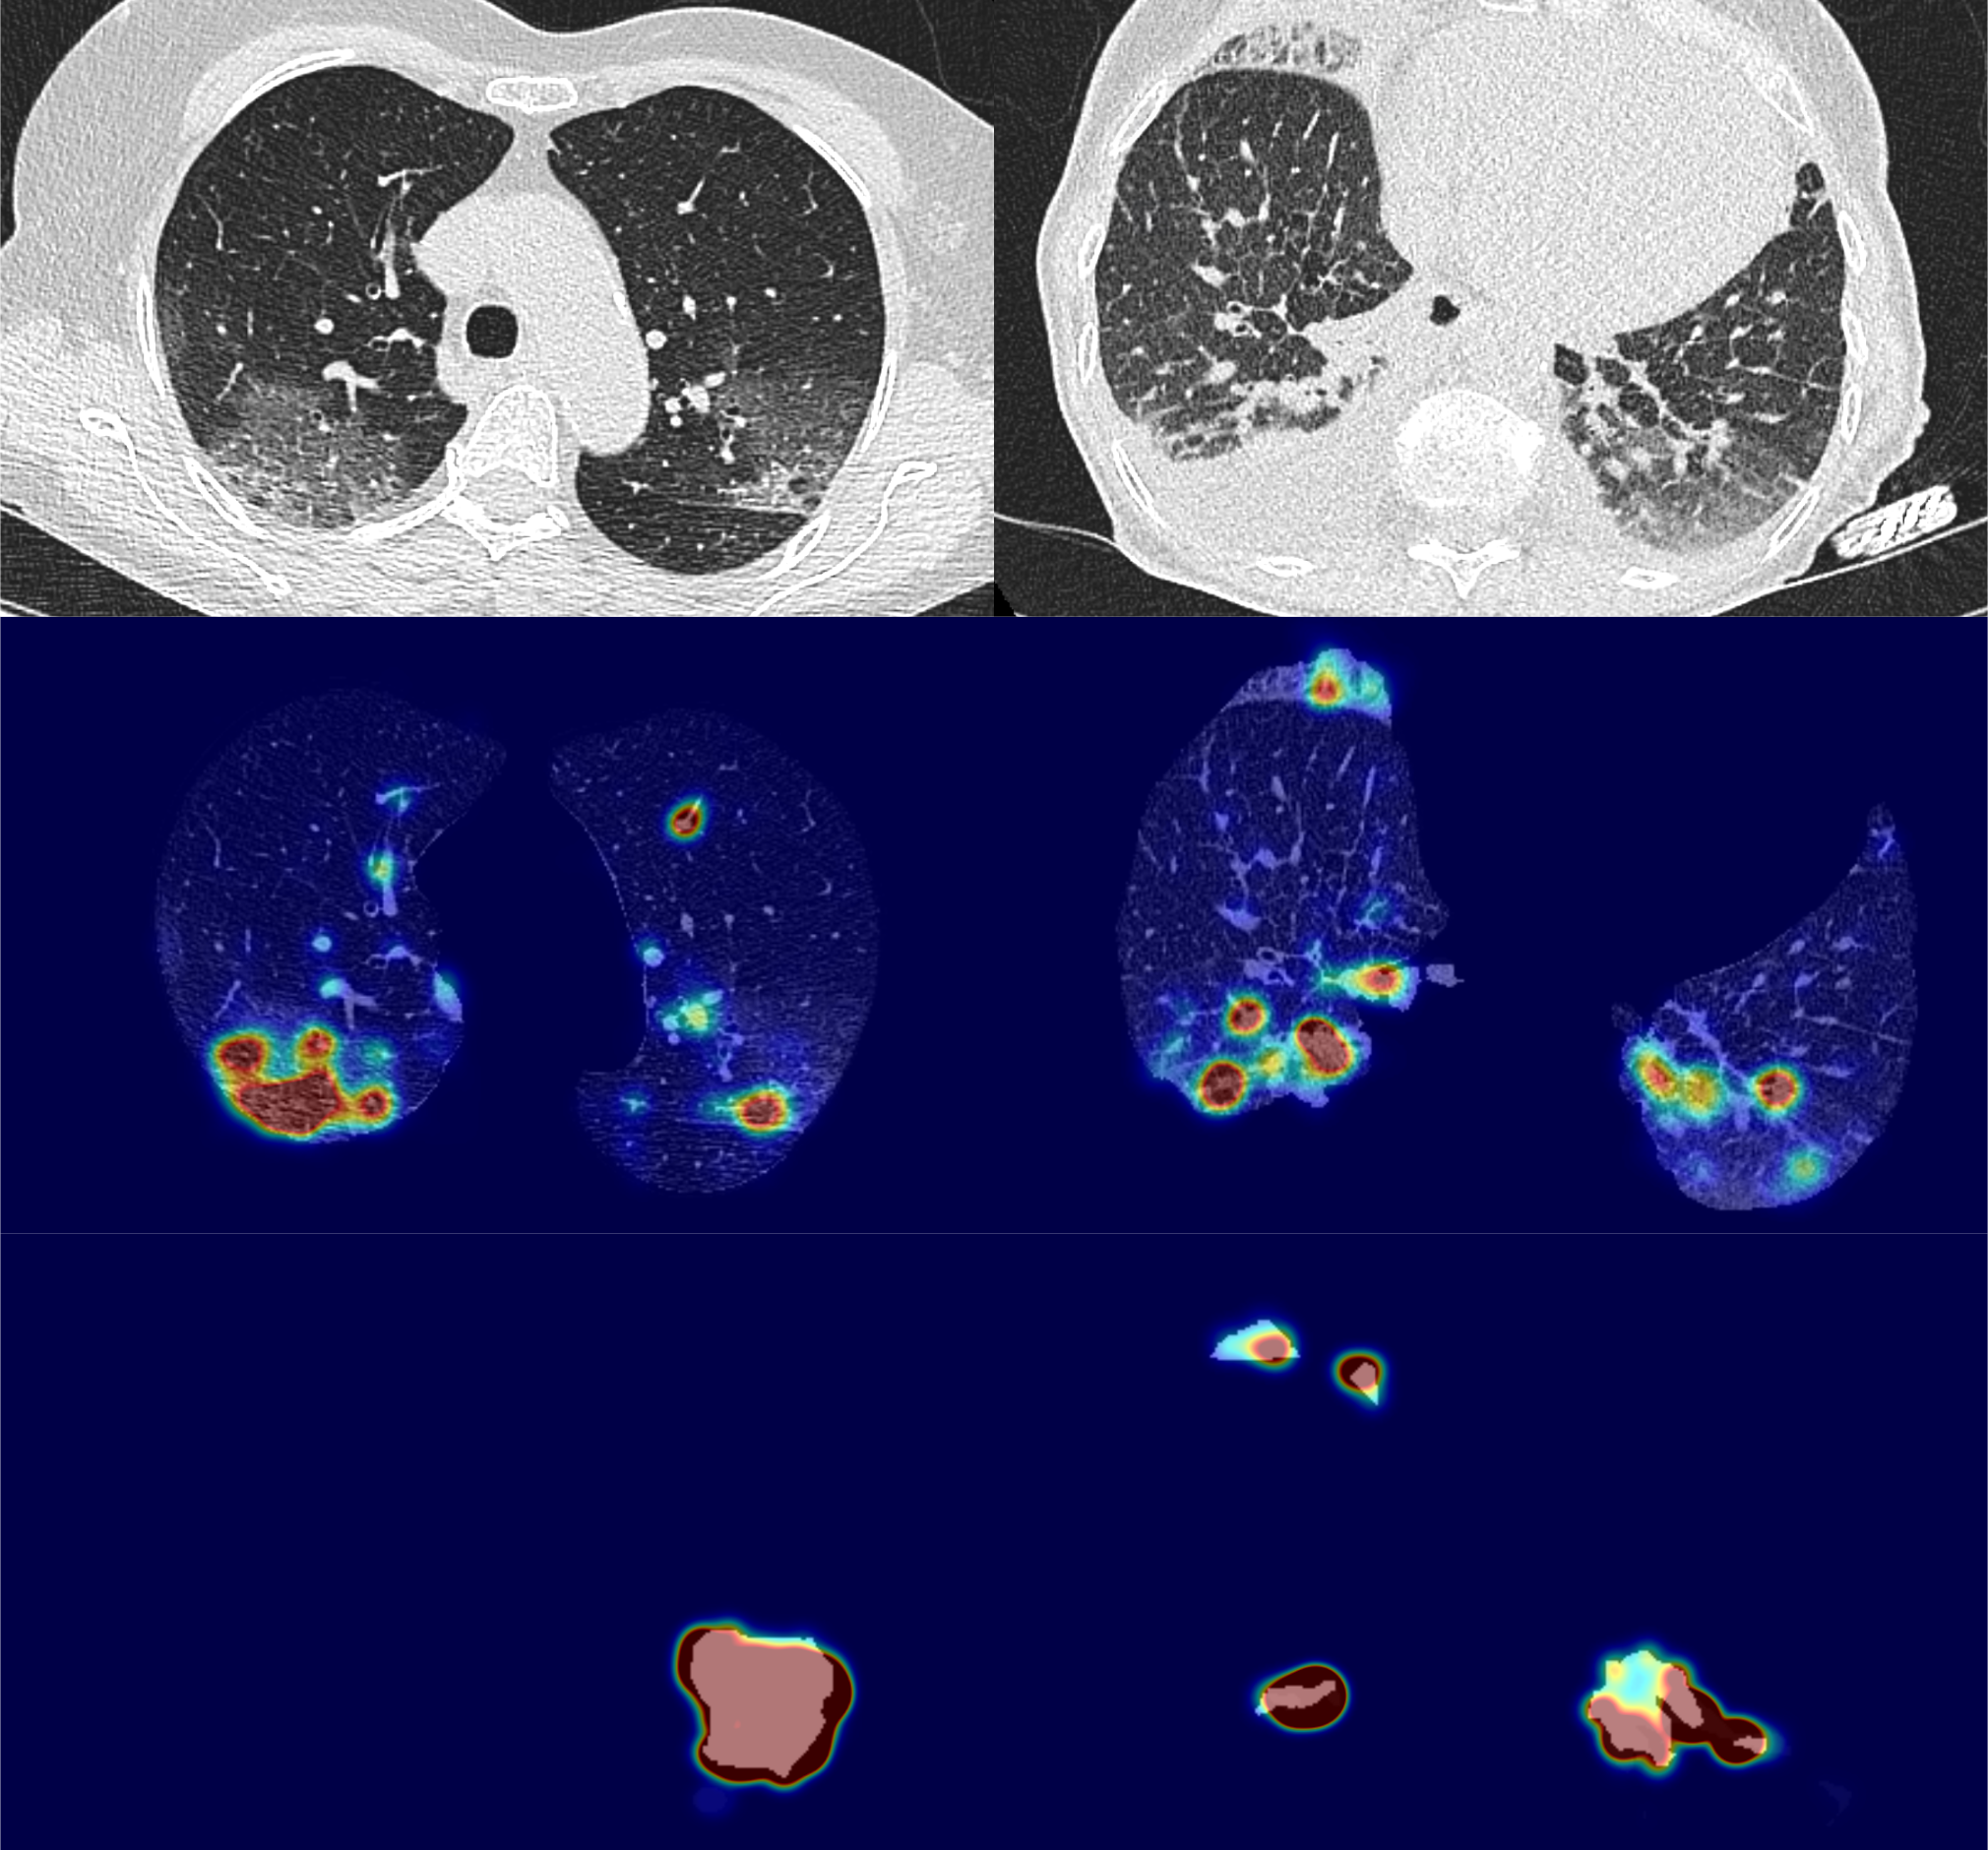

Some examples of true predictions are shown in Figure 9.(A-F) and of false predictions in Figure 9.(G-I). Lesions are indicated with a red arrow. Though the patient in Figure 9.E has large lesions, it is correctly classified as COVID-19 negative. For the case in Figure 9.G, there is a small lesion in the left lung, the case was wrongly classified as COVID-19 positive. For the false negative Figure 9.I, the system missed the very subtle ground glass opacity.